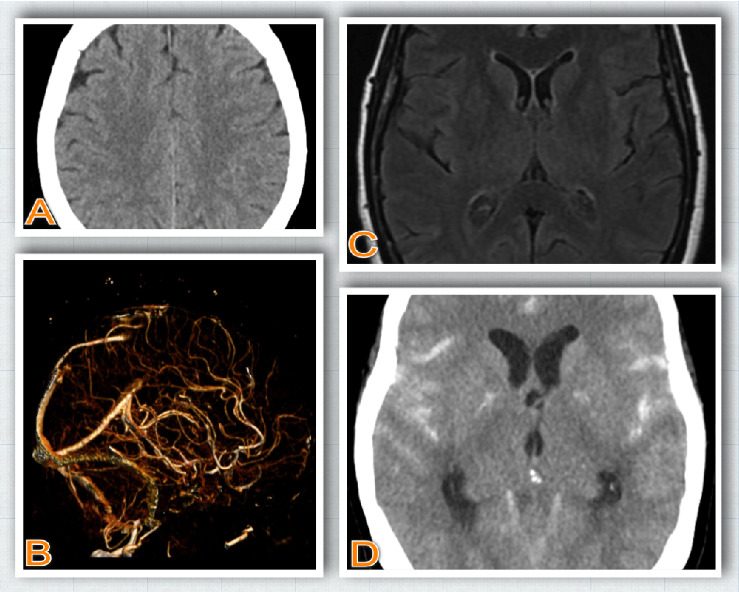

Subarachnoid hemorrhage (SAH) is a life-threatening condition most commonly caused by aneurysmal rupture. Sentinel headaches, often described as the "worst headache of life" or a "thunderclap headache," are critical warning signs that may precede SAH. However, atypical headaches can complicate early diagnosis. Oculomotor nerve palsy, though rare, may occur as a complication of both aneurysmal and nonaneurysmal SAH. We report a unique case of a 64-year-old woman who initially presented with atypical headache followed by isolated oculomotor nerve palsy, preceding the onset of a nonaneurysmal SAH. This case highlights isolated oculomotor palsy as a potential unrecognized sentinel sign of SAH.